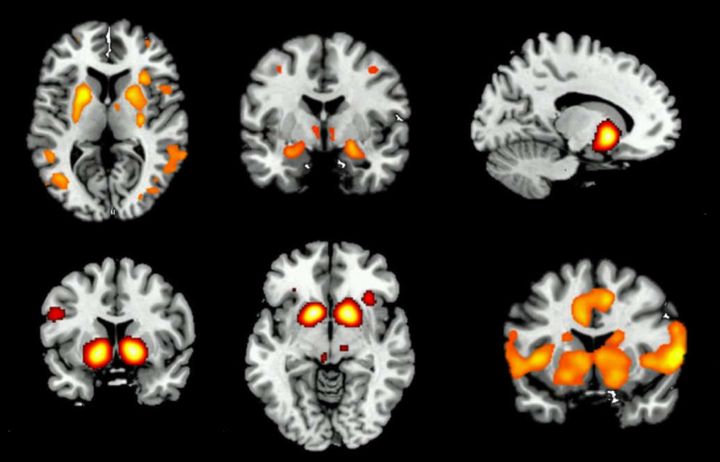

Brain scans

NCORE

In this study (NCORE: Neural Correlates of Reward and Emotion in opioid dependence), we are investigating the effects of opioid dependence on brain function, with the aim of improving treatment for detoxification and relapse prevention.

Our research uses brain-imaging techniques to detect subtle changes in brain function while performing psychological tasks. These tasks measure brain processes that are important in opioid dependence. We will investigate the effects of aprepitant on brain function in opioid-dependent individuals during methadone treatment, and again, after achieving abstinence from methadone.